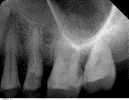

在根管治疗中,由于根管形态复杂异常如根尖狭窄或弯曲及治疗器械金属疲劳,手术器械有可能在根管内折断。折断部位位于根管弯曲上部时可用超声器械将其取出;若折断器械位于根管弯曲部下方或根尖部,为避免造成牙体组织的过度损伤,不必强行取出。可采用其他器械从折断部位旁通过到达根尖部的方法完成根管治疗。折断器械位于根管内未取出,对全身系统健康无任何影响。